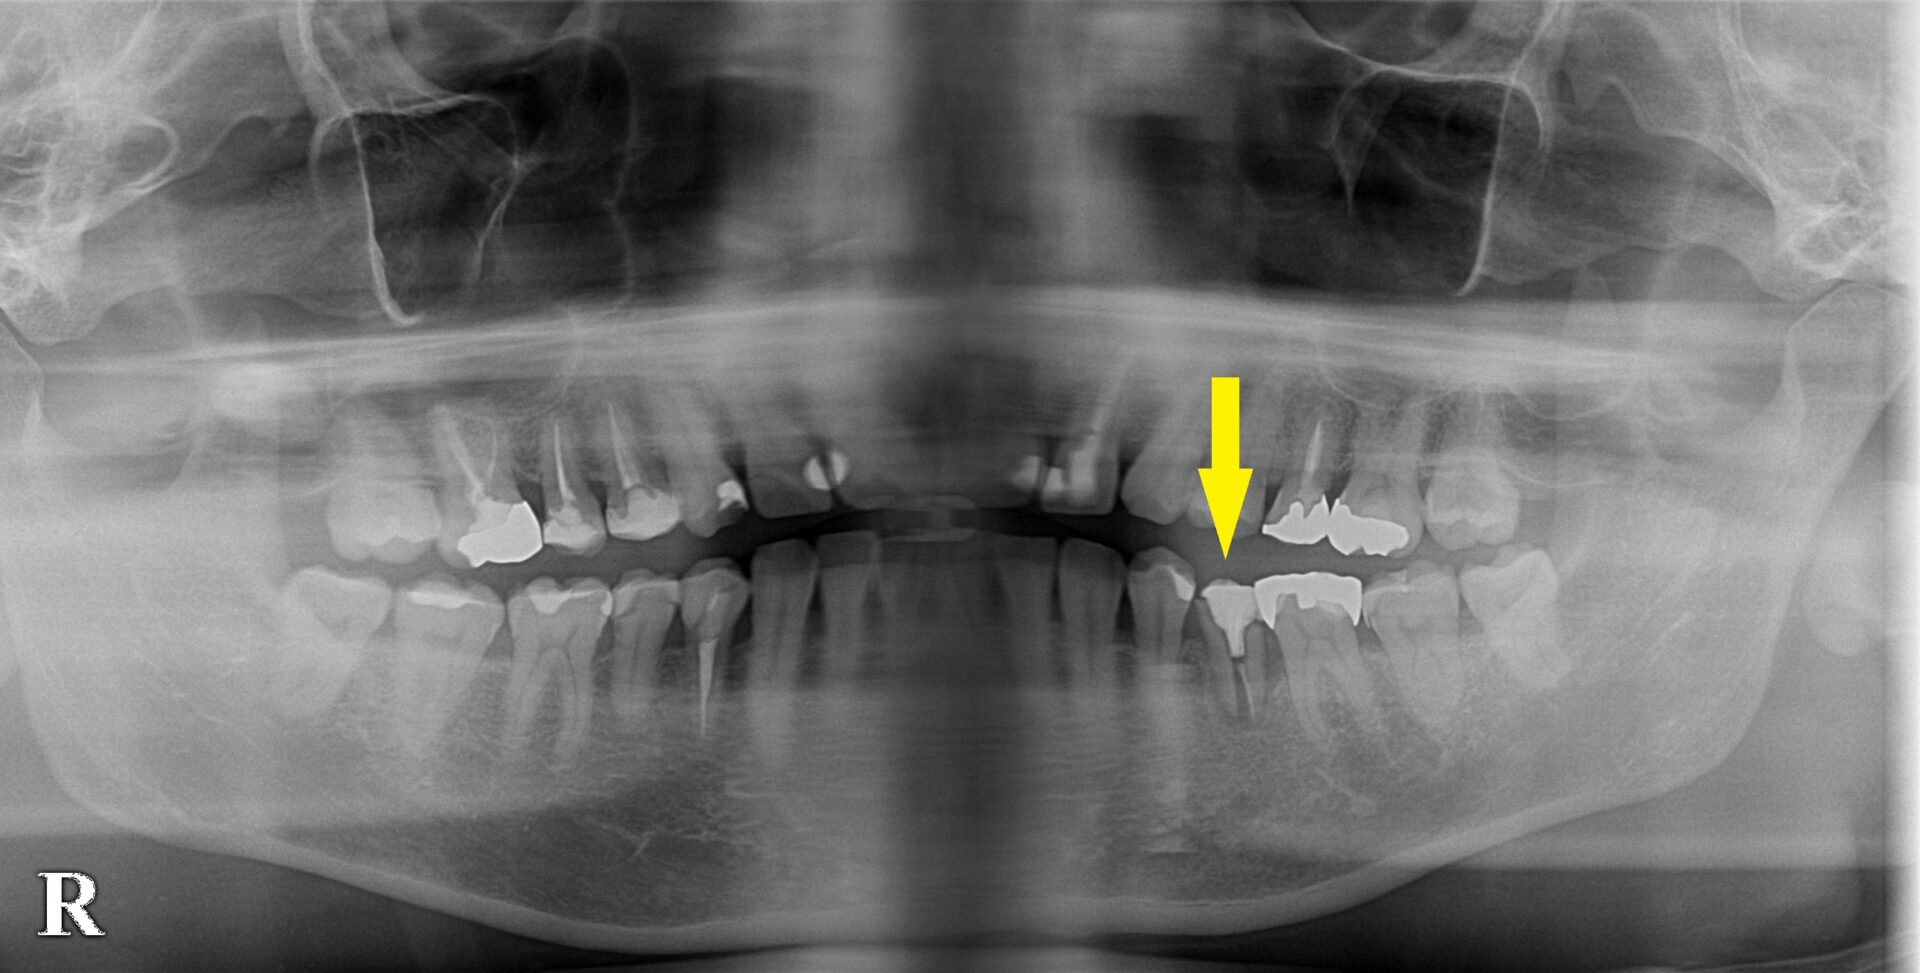

下顎小臼歯の骨造成症例

左下顎の第二小臼歯が破折してしまい、抜歯が必要でした。

抜歯する前にCT撮影したところ、外側の骨が吸収されてしまっていた(下の写真、下段左)ので、抜歯即時インプラント埋入ではなくて、まず抜歯して、数か月治癒を待つこととしました。